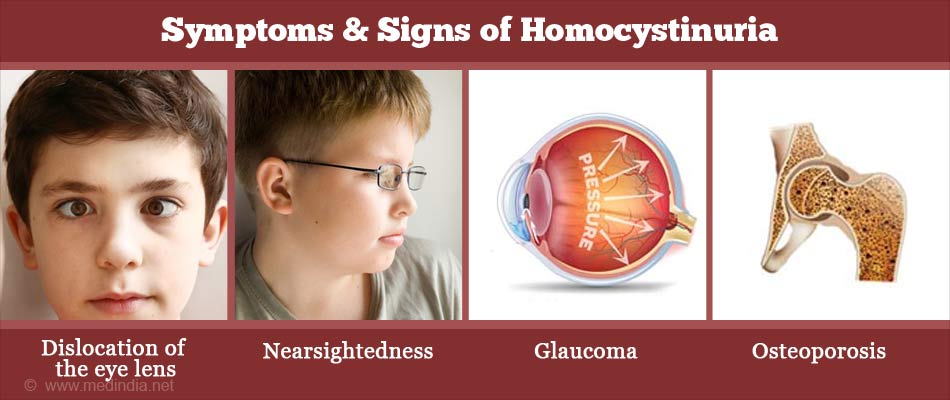

Homocystinuria

Classical homocystinuria, also known as cystathionine beta synthase deficiency or CBS deficiency,is an inherited disorder of the metabolism of the amino acid methionine due to a deficiency of cystathionine beta synthase.It is an inherited autosomal recessive trait, which means a child needs to inherit a copy of the defective gene from both parents to be affected or can be acquired with a deficiency of B6, B12, or folate.